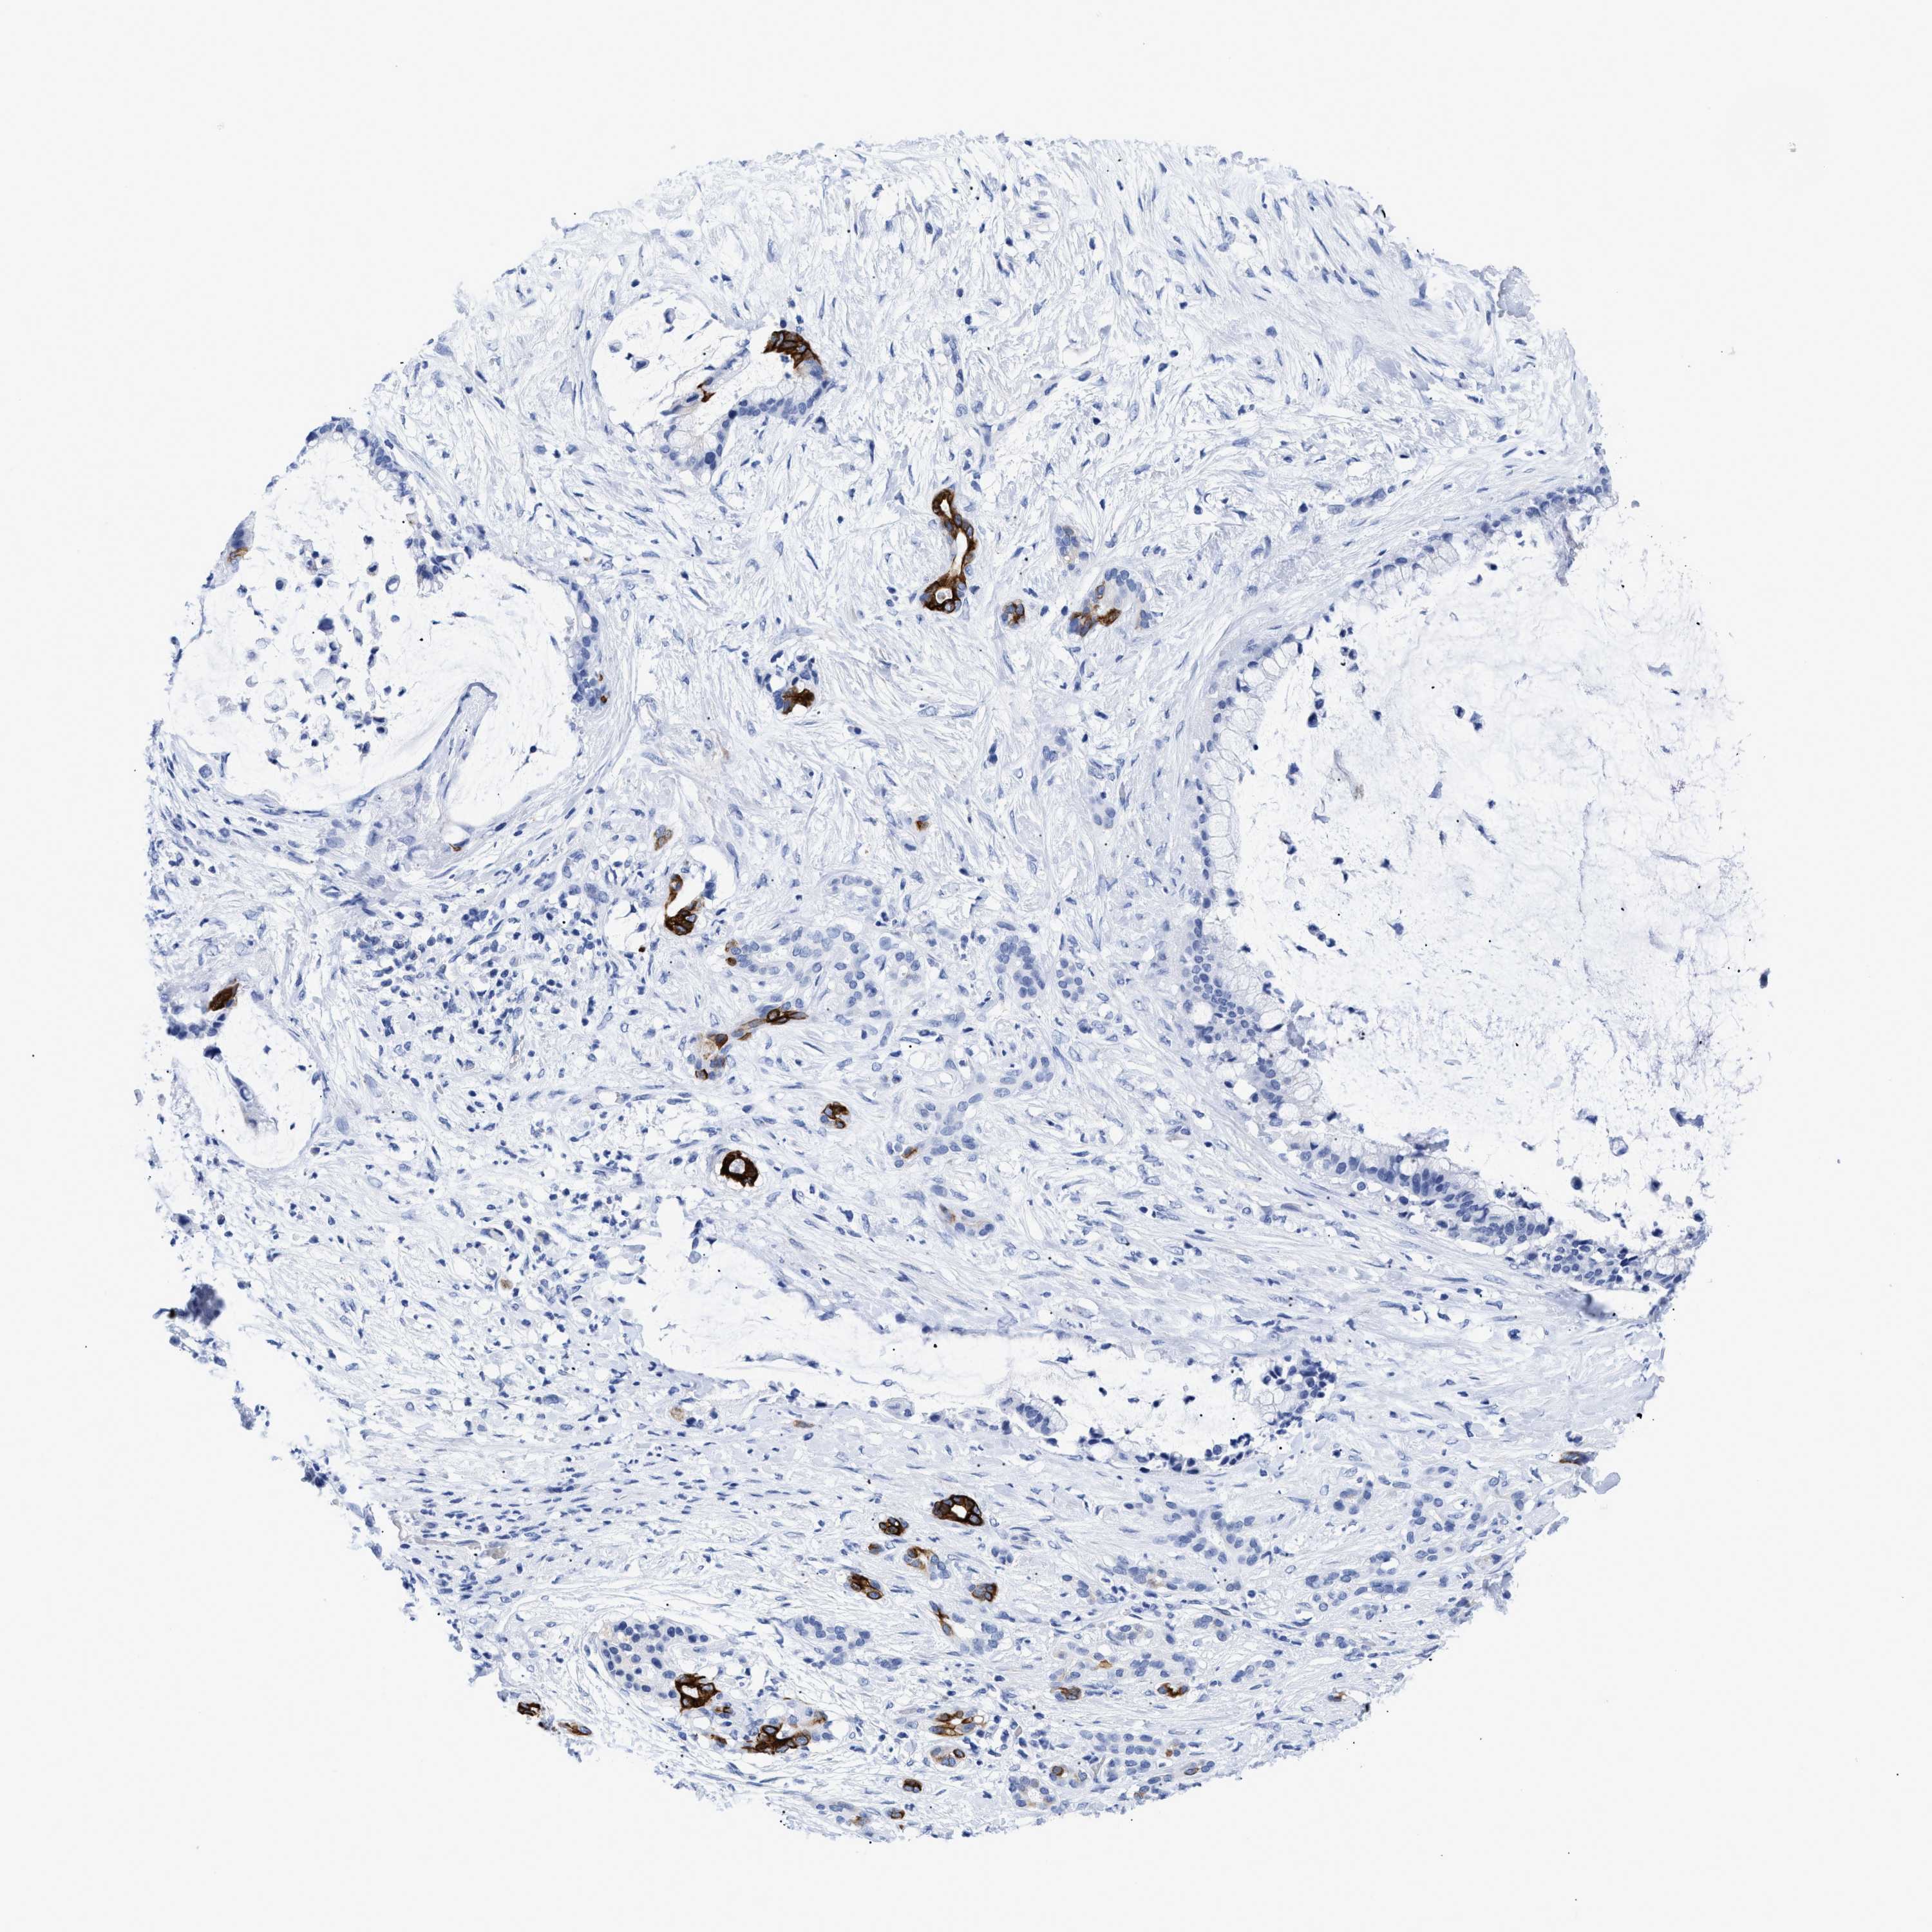

PANCREATIC CANCER - Protein expressioni

A mouse-over function shows sample information and annotation data. Click on an image to view it in a full screen mode. Samples can be filtered based on level of antibody staining by selecting one or several of the following categories: high, medium, low and not detected. The assay and annotation is described here.

Note that samples used for immunohistochemistry by the Human Protein Atlas do not correspond to samples in the TCGA dataset.

Antibody stainingi

Antibody staining in the annotated cell types in the current human tissue is reported as not detected, low, medium, or high, based on conventional immunohistochemistry profiling in selected tissues. This score is based on the combination of the staining intensity and fraction of stained cells.

Each image is clickable and will lead to virtual microscopy that enables deeper exploration of all samples and also displays staining intensity scores, fraction scores and subcellular localization as well as patient and tissue information for each sample.

Antibody HPA018221

Staining

High

Medium

Low

Not detected

Intensity

Strong

Moderate

Weak

Negative

Quantity

>75%

75%-25%

<25%

None

Location

Nuclear

Cytoplasmic/membranous

Cytoplasmic/membranous,nuclear

Adenocarcinoma, NOS